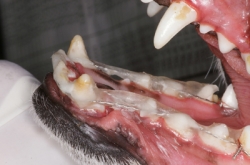

La periodontitis se clasifica como “Periodontitis leve” cuando el tejido óseo se ha destruido máximo en el tercio cervical; “Periodontitis moderada” cuando la destrucción ósea ha llegado al tercio medio de la raíz y “Periodontitis severa” cuando la destrucción ósea ha llegado al tercio apical de la raíz. La movilidad dental ligera aparece en la periodontitis moderada y la movilidad dental excesiva aparece en la periodontitis severa.

Haz CLICK sobre la imagen para ver descripción.